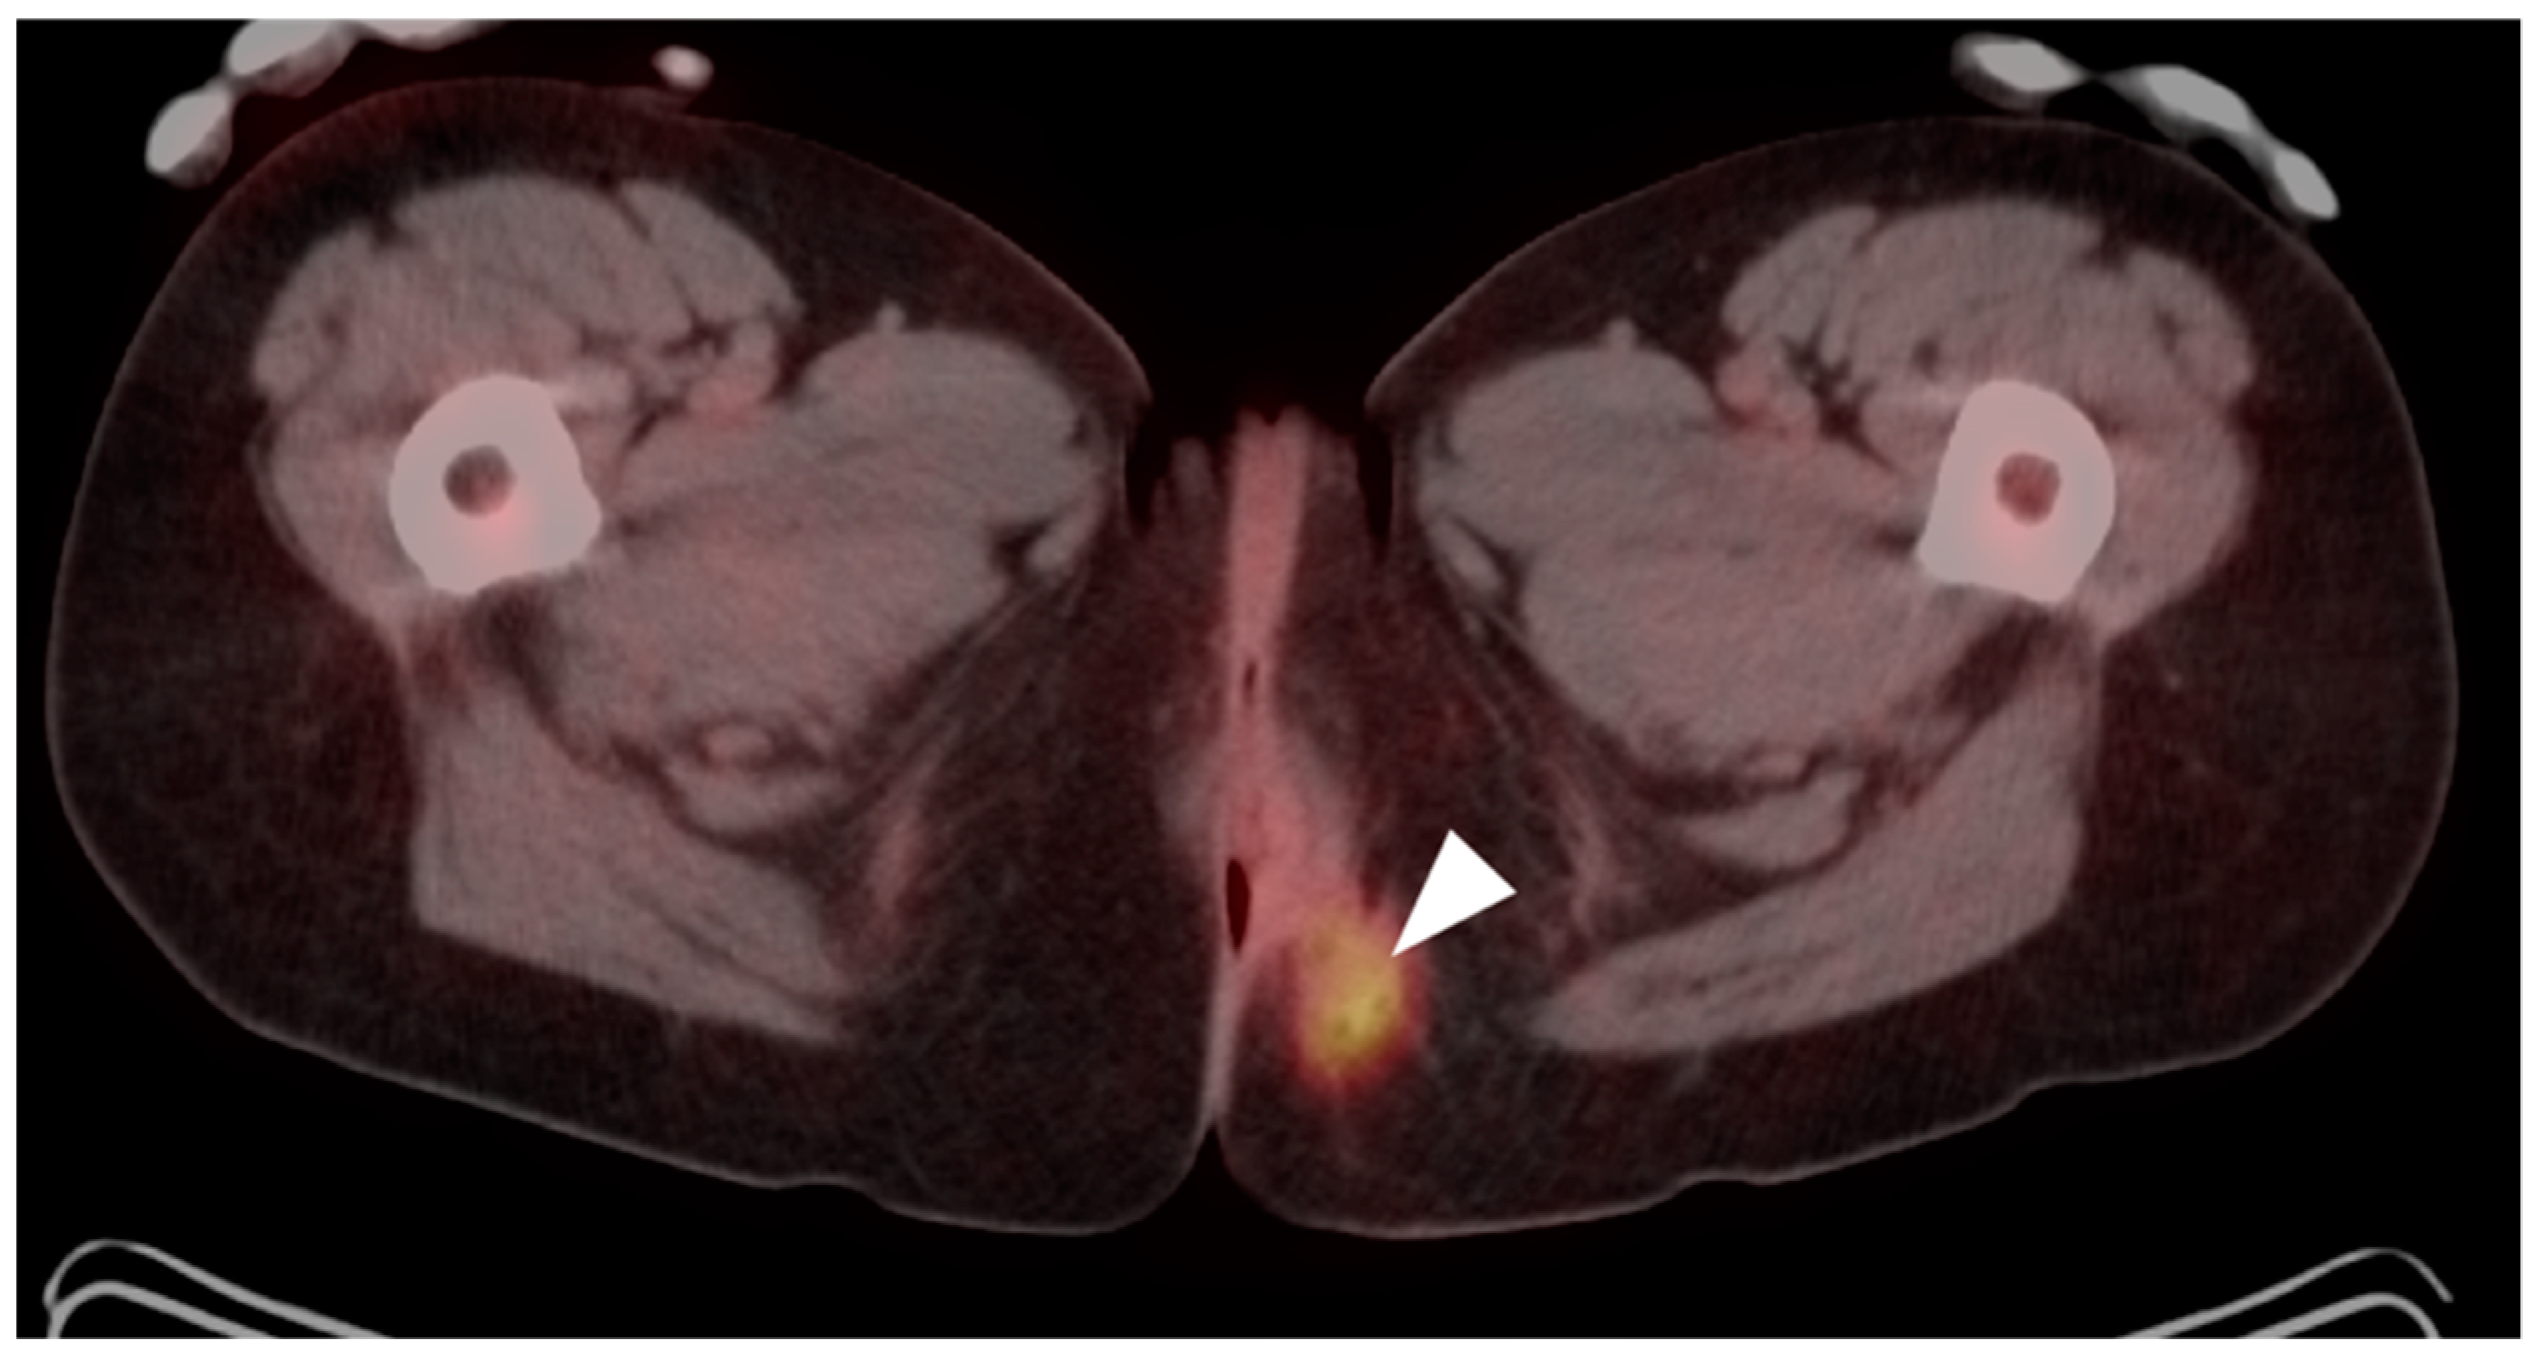

10. Anal Carcinoma